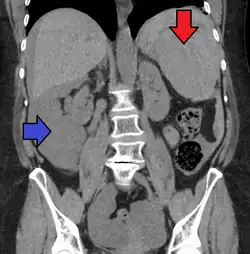

Splenic rupture is usually evaluated by FAST ultrasound of the abdomen.[5] Generally this is not specific to splenic injury; however, it is useful to determine the presence of free floating blood in the peritoneum.[5] A diagnostic peritoneal lavage, while not ideal, may be used to evaluate the presence of internal bleeding a person who is hemodynamically unstable.[6] The FAST exam typically serves to evaluate the need to perform a CT scan.[6] Computed tomography with IV contrast is the preferred imaging study as it can provide high quality images of the full peritoneal cavity.[5]

Organ injury scale

AAST (American Association for the Surgery of Trauma) Organ Injury Scaling: Splenic Injury Grading[7]